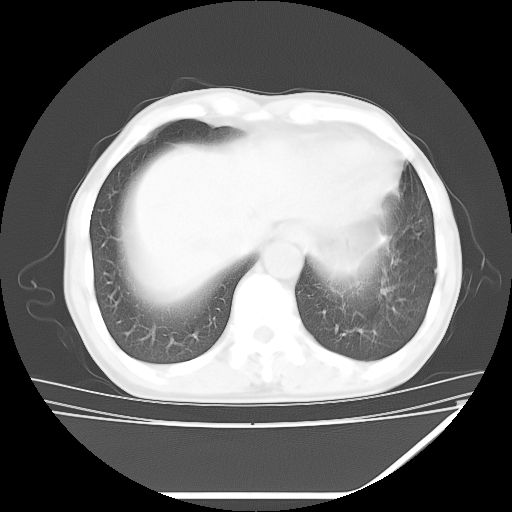

男,59岁,“结核性胸膜炎”30余年,胸部经常疼痛,多次x检查提示“肺部”炎症。腹部疼痛5日,b超提示:“肝内短管结石,余显示不清,建议进一步检查。”

两肺结核并右侧胸腔积液;脾脏、腹腔及腹膜后淋巴结结核[陈旧性];肝内胆管结石

两肺结核并右侧胸腔积液;脾脏、腹腔及腹膜后淋巴结结核[陈旧性];肝内胆管结石。直肠息肉?

均为结核所致,右侧少量胸腔积液